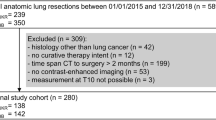

One radiologist with ten years of experience in chest and musculoskeletal imaging used a semi-automatic tool of an opens source software (3D Slicer, www.slicer.org) to segment the spinal muscles of each patient at the level of the 11th dorsal vertebra, covering a volume of 1 cm height, and applying the usual Hu range for muscle assessment (− 29 to 150 Hu) [24, 25] (Fig. 1A, B, C). Aiming to standardize the approach and guarantee repeatability, the first slice including the upper plate of the 11th dorsal vertebra was considered as reference point to start the segmentation.

Graphic representation of the study design: in A axial HRCT scan indicating the examined population, composed of candidates to bilateral pulmonary transplant referring to our tertiary center; in B the selection of the paravertebral muscles at the level of the 11th dorsal vertebra with an extension of 1 cm height, used for the segmentation; in C the segmented muscle area, performed applying the threshold − 29 to + 150 Hu; in D the examined volume from which were extracted the radiomic features; in E the factor analysis applied for variables reduction

We considered the value < 30 Hu of the examined volume as threshold for the definition of muscle loss [15, 26, 27].

For the radiomics analysis, the radiomics plugin of 3D Slicer which encapsulates pyRadiomics library was applied. The previously segmented volume was loaded in the radiomics module interface. Range re-segmentation and intensity outlier filtering were not needed since the range for muscle assessment (− 29 to 150 Hu) was previously applied [28].

Aiming to avoid model overfitting due to the small sample size, only 72 radiomic features extracted (Fig. 1D). The radiomic features were of first and second order: intensity-based features (FOS) and texture features [gray-level co-occurrence matrix (GLCM) as well as gray-level run length matrix (GLRLM)]. Among the FOS, mean, standard deviation, skewness, kurtosis, and energy were included, while for the GLCM, for instance, inverse variance, sum average, joint entropy, and cluster shade were extracted; last, among the GLRLM, short run emphasis, run percentage, and long run low gray level emphasis were included.

Factor analysis was applied to select highly correlating radiomic features (Fig. 1E).